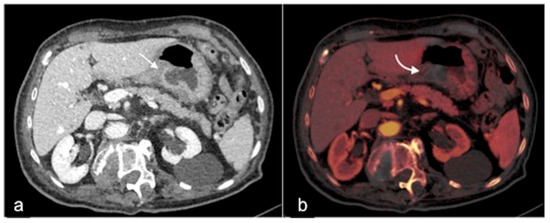

2.4. Dual-Energy CTA (DECTA)

- Trabzonlu, T.A.; Mozaffary, A.; Kim, D.; Yaghmai, V. Dual-energy CT evaluation of gastrointestinal bleeding. Abdom. Radiol. 2020, 45, 1–14. [Google Scholar] [CrossRef] [PubMed]

| DECTA post-processing | 40–60 keV (i.e., virtual monoenergetic), iodine density, virtual non-contrast and standard mixed series | 40–60 keV (i.e., virtual monoenergetic), iodine density, virtual non-contrast and standard mixed series |